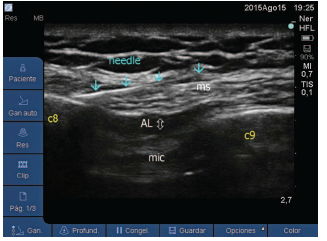

All patients described signed the informed consent prior to the administration of the anesthetic-analgesia technique in the series of cases (modified BRILMA). This fascial block in performed under ultrasound vision (M-Turbo portable equipment; Sonosite, Bothell, WA), using a 6 to 15-Hz high-frequency linear probe and an 80-mm Ultra-plex 360 needle (B. Braun, Melsungen, Germany). With the patient in supine decubitus, the probe is placed in the sagittal plane of the mid-axillary line (Fig. 1), to identify the fascial plane between the anterior serratus muscle and the external intercostal muscle. The needle is introduced from caudal to cephalic until the tip is placed at the level of the eighth rib, where 15 mL of levobupivacaine are administered into the fascial space, making sure that the agent is properly scattered (Fig. 2).